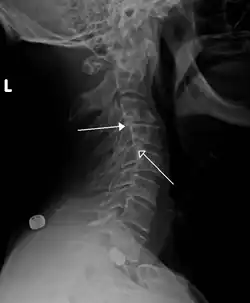

Класс 1 ретролистезы C3 на C4 и C4 на C5